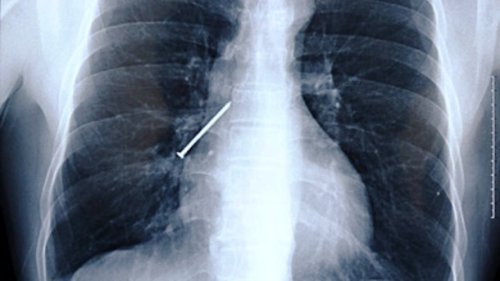

Бутерброды с бананом, картошка фри с молочным коктейлем, соленья с арахисовым маслом... У некоторых людей есть необычные привычки питания и предпочтения в еде. Однако после прочтения этой статьи вы сочтёте эти маленькие отклонения абсолютно приемлемыми. Ознакомьтесь с этими странными предметами, которые были найдены в человеческом кишечнике (которые, вероятно, заставили поёжиться даже самых опытных хирургов). 25. Бутылка Мужчина обратился в китайскую больницу с жалобами на боли в животе. То, что врачи обнаружили, было шокирующим и довольно смущающим для бедолаги. Оказалось, причиной брюшной боли была бутылка, которую удалили хирургическим путём. 24. Столовые приборы Маргарет Далман (Margaret Daalman) из Нидерландов попала в больницу с болями в желудке. Хирурги в Роттердамской больнице отправили её на рентген и были потрясены, когда изображение показало 78 различных предметов столовых приборов в желудке 52-летней женщины. К счастью, она ела только ложки и вилки, а не ножи. 23. Батарейки Каждый год регистрируется несколько случаев, когда дети съедают батарейки. К примеру, в декабре 2013 года 13-месячный мальчик из города Лестер (Leicester), Англия, умер от внутреннего кровотечения после проглатывания батарейки, которую он нашёл в своём детском саду. 22. Живые лягушки Янг Дингкай (Yang Dingcai) с юго-востока Китая говорит, что 40-летняя привычка глотания живых лягушек и крыс помогла ему избежать проблем с кишечником и сделала его сильным. 21. Гвоздь Китайский плотник Ли Сянъян (Li Xiangyang) держал гвоздь между своих зубов, когда он вдруг закашлялся и проглотил его. Он был доставлен в больницу, где врачи сделали рентгеновский снимок и нашли гвоздь в правом лёгком. Профессор Ху Кэ (Hu Ke) попытался удалить его с помощью бронхоскопа через его горло. Однако в тот момент, когда он был уже на грани того, чтобы вытянуть гвоздь, Ли снова закашлялся и всосал его обратно. На этот раз гвоздь оказался в его левом лёгком. Ху попытался снова, но в последнюю минуту, Ли невольно сглотнул и гвоздь снова исчез. В конце концов, врачи обнаружили гвоздь и, наконец, смогли удалить его с помощью гастроскопического зажима. 20. Ручная граната Рентген выявил ручную гранату в желудке террориста. Очевидно, он не продумал свой план достаточно хорошо, потому что у него не было возможности на самом деле детонировать гранату. 19. Ложка 33-летняя женщина пыталась ложкой удалить рыбную кость, попавшую в её гортань. Она случайно проглотила ложку, и её пришлось отвезти прямиком в операционную, чтобы удалить ложку хирургическим путём. 18. Пуля Четырёхлетняя девочка из города Тхане (Thane), Индия, проглотила пулю в районе Локманья Нагар (Lokmanya Nagar). Девочка играла в окрестности, когда она нашла пулю, лежавшую на земле. Предположив, что это был шоколад, она взяла её и положила в рот. Девочку отвезли в больницу, где врачам удалось успешно вытащить свинец без хирургического вмешательства. 17. Наркотики Нигерийца, пойманного в Международном аэропорту Куала-Лумпур (Kuala Lumpur International Airport) в Малайзии, доставили в больницу, где рентген показал наличие инородного предмета в его желудке. Предметом, как оказалось позднее, были 54 капсулы метамфетамина. 16. Живой угорь Мужчина из Китая обратился в больницу после того, как по сообщениям, в нём застрял живой угорь. Мужчина вставил 50-сантиметрового азиатского рисового угря себе в анус, увидев, как это сделали в порно. Поэтому ему пришлось выдержать операцию, которая длилась всю ночь, чтобы извлечь этого угря. Как сообщается, члены команды врачей сказали, что угорь, который «просто пытался найти выход», был жив, когда его вытащили, но вскоре скончался. 15. Обручальное кольцо Кейтлин Уиппл (Kaitlin Whipple) проглотила обручальное кольцо, которое её бойфренд Рид Харрис (Reed Harris) поставил в её мороженое. После того, как Кейтлин проглотила его, она с недоверием отнеслась к заверениям своего приятеля о том, что он поставил кольцо в её мороженое. Риду пришлось отвезти её на рентген, чтобы это доказать. 14. Ножницы 27-летний Конг Лин (Kong Lin) использовал 10 сантиметровую пару маникюрных ножниц в качестве зубочистки после еды. Однако когда один из его друзей рассказал анекдот, Конг рассмеялся и быстро проглотил ножницы. 13. Самолёт Мишель Лотито (Michel Lotito) являлся французским конферансье, известным как человек, который мог съесть несъедобное. Он также был известен как «Месьё Съешьвсё» (Monsieur Mangetout). Во время своего представления Лотито поглощал металл, стекло, резину и другие материалы от таких предметов, как велосипеды, телевизоры, или даже самолёт (Cessna 150, если быть точным). Съедение самолёта заняло у него около двух лет. Лотито не часто страдал от вредных последствий из-за своей диеты, даже несмотря на то, что он ел материалы, которые, как правило, считаются ядовитыми. Он, видимо, обладал желудком и кишечником, чьи стенки были двойной толщины, и его пищеварительные кислоты предположительно были необычайно мощными. 12. Мобильный телефон На этом удивительном рентгеновском снимке, сделанном в тюрьме в Сан-Сальвадор (San Salvador) видно, насколько далеко могут зайти люди, чтобы не потерять связь. 11. Монеты 62-летний мужчина с историей психиатрических проблем, отправился в отделение неотложной помощи в 2002 году, мучаясь от болей в животе. Врачи были шокированы, когда они обнаружили причину боли пациента - в его животе было приблизительно 350 монет (на общую сумму в 650 долларов) наряду с различными ожерельями и иглами. Всё это было настолько тяжёлым, что его живот провис между его бёдер. 10. Ручка 76-летняя женщина посетила гастроэнтеролога из-за желудочных проблем, связанных, в том числе с потерей веса и диареей. Рентген показал ручку, застрявшую в желудке женщины. После того, как ручка была извлечена из кишечника, где она находилась в течение 24 лет, оказалось, что она всё ещё была в рабочем состоянии. 9. Пружины от кровати Рентгеновские снимки из центральной тюрьмы в городе Роли (Raleigh), штат Северная Каролина, показали такие предметы, как пружины от кровати, которые заключённые глотали, чтобы получить возможность поездки в больницу, расположенную на воле. 8. Человеческий плод Санджу Бхагат (Sanju Bhagat) из Индии постоянно являлся предметом насмешек из-за своего чрезмерно большого живота. Однажды ночью его доставили в больницу из-за одышки и сильной боли. Когда доктора попытались удалить то, что, как они думали, было опухолью, они были шокированы, увидев частично сформировавшийся человеческий плод. 7. Ключ 18-летний студент компьютерного дизайна проглотил 5-сантиметровый ключ на вечеринке, чтобы помешать своим друзьям отвезти его домой, после того как они решили, что он уже достаточно выпил. Врачи отправили его домой, сказав ему, чтобы он позволил природе сделать своё дело, и ключ появился 31 час спустя. 6. Крупная галька В 2006 году девушка из Фошань (Foshan), Китай, проглотила более 20 камней гальки в минуту гнева после большой ссоры со своим бойфрендом. Изначально, она думала, что камни выйдут сами по себе но, к сожалению, они этого не сделали и оставались в её теле в течение следующих нескольких дней. 5. Магниты Когда 8-летняя ученица Хэйли Ленц (Haley Lents) из города Хантингбург (Huntingburg), штат Индиана, нашла блестящие металлические предметы, разбросанные по дому она, естественно, предположила, что они были конфетами. Вскоре её кишечник был заполнен магнитами, и её пришлось доставить в больницу, чтобы помешать их скреплению внутри её кишечника. 4. Электрическая лампочка Когда врачи в Пакистане удалили лампочку из толстого кишечника заключённого, у него не было никакого объяснения для этой крайне необычной находки, и он казался настолько же ошарашенным, как и все остальные. 3. Хирургический пинцет 57-летний Дариуш Мазарей (Daryoush Mazarei) испытывал сильную боль после обширной операции. Несмотря на хронический дискомфорт и боль, Мазарею неоднократно говорили, что с ним всё в порядке в физическом плане. Когда врачи Мазарея наконец сделали ему компьютерную томографию, они увидели большой инородный предмет, находившийся в его животе. После повторного открытия брюшной полости пациента, хирурги нашли пару медицинских пинцетов, которые были случайно оставлены внутри мужчины во время последней операции. 2. Комок волос Неизвестная 18-летняя женщина из Новой Англии, США, попала в больницу с болями в желудке и потерей веса. В животе врачи обнаружили огромный комок волос, который занимал почти весь её живот. Пациентка сказала, что у нее есть привычка кушать собственные волосы. Ей пришлось перенести традиционную операцию, чтобы убедиться в том, что весь комок шерсти был удалён. 1. Вилка 40-летний Ли Гарднер (Lee Gardner), случайно проглотил вилку длиной в 22 сантиметра. Врачи сказали ему, что вилка быстро пройдёт по организму, но это оказалось не так. Спустя 10 лет он начал рвать кровью и страдать от ужасных спазмов желудка. Он перенёс операцию, чтобы удалить вилку в Барнсли, Англия и полностью выздоровел. |